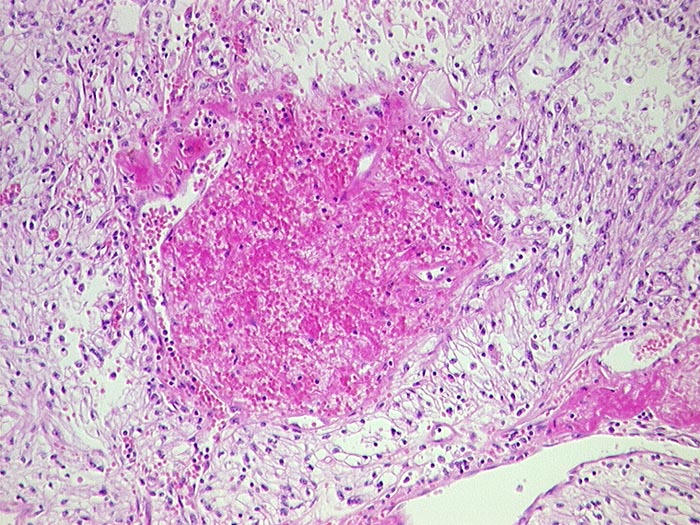

p/ Hellzelliges Nierenzellkarzinom, FNP

Hellzelliges Nierenzellkarzinom, FNP

Die Tumorzellen sind in der Regel etwa zweimal so gross wie normale Tubulusepithelien. Zytoplasma ist reichlich vorhanden, blass und vakuolisiert. Hyaline intrazytoplasmatische Einschlusskörperchen können gelegentlich vorhanden sein. Die Zellkerne sind abhängig vom Differenzierungsgrad unterschiedlich gross und atypisch. Die Grösse der Nukleolen schwankt entsprechend von unscheinbar bis sehr gross. Histiozyten, Nebennierenrindentumoren oder normale Nebennierenrindenzellen können aufgrund ihrer ähnlichen Zytomorphologie ein hellzelliges Karzinom vortäuschen. Der Nachweis von Drüsen, Papillen oder reichlich Glykogen spricht eher für das Nierenkarzinom.